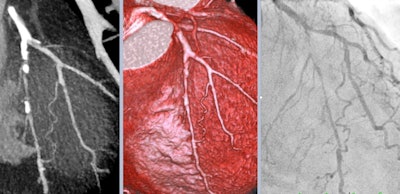

Achenbach is chairman of cardiology and a professor of medicine at the University of Erlangen, Germany, and he became ESC president in September 2020. He won the 2017 Minnie award for Most Influential Radiology Researcher. His research interests focus on cardiovascular imaging, mainly CT, for the early detection and characterization of coronary atherosclerosis, and for the support of coronary and cardiovascular interventional procedures.

The option to rapidly rule out coronary artery disease (CAD) in patients with low-risk acute chest pain by CT is a very attractive one, though, and it is used more than before. This is done with the aim to discharge patients immediately from the emergency room and avoid having to admit them to the wards.

For cardiac CT in patients with COVID-19, if the pretest likelihood of CAD is high, I am not a big fan. Such patients may then end up needing two tests -- a CT first and then invasive angiography. Then two teams will have patient contact with infection risks. So once again it depends a lot on pretest likelihood.